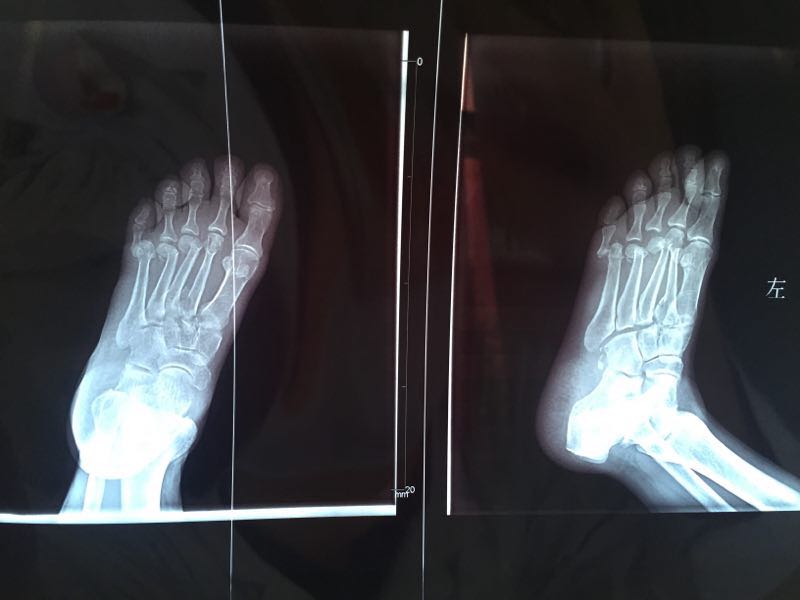

患者女性,67岁。 主诉:摔伤后左足疼痛、肿胀伴活动受限8+小时。 现病史:8+小时前患者骑自行车时不慎摔倒,织左足着地,伤后出现左足疼痛伴活动受限。就诊于当地医院,查左足X片示:第2、3跖骨基底部骨折,第3、4跖骨头骨折,第5跖趾关节脱位。患者为求进一步诊治,就诊于我院急诊,急诊以“左足Lisfranc损伤”收入我科。 既往史高血压病1年。

查体:左足背、左足外侧皮肤软组织肿胀,局部皮肤散在瘀斑形成,左足背内侧皮肤可见一大小约2*2cm水疱。左足背侧皮肤软组织触痛明显,左足第1、2趾活动受限,左足第3、4、5趾活动障碍。 辅助检查: 左足X片示:第2、3跖骨基底部骨折,第3、4跖骨头骨折,第5跖趾关节脱位。